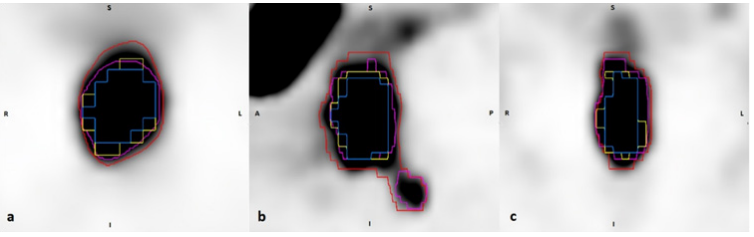

A total of 33 prospectively acquired PET study sets (10 pre– and 23 post–treatment) were available for analysis. The number of post–treatment imaging studies was limited by incomplete referral and attendance. Semi–automated methods, SUV–gradient, T40, T50, and T60 produced contours on 15, 25, 18, and 14 study sets respectively, compared to 11 produced by the clinician (Manual method). Figure 2 demonstrates the resultant volumes on one representative patient’s study set. For comparative analysis to our clinical standard, Manual method, only the 11 study sets, comprising ten pre–treatment and one post–treatment, were considered. Resultant contour descriptors are summarised in Table 1 and Table 2.

Figure 2 Axial (a), Sagittal (b), and Coronal (c) images demonstrating contour volumes derived from Manual (pink), T40 (red), T50 (yellow), T60 (blue) and SUV-gradient (orange).